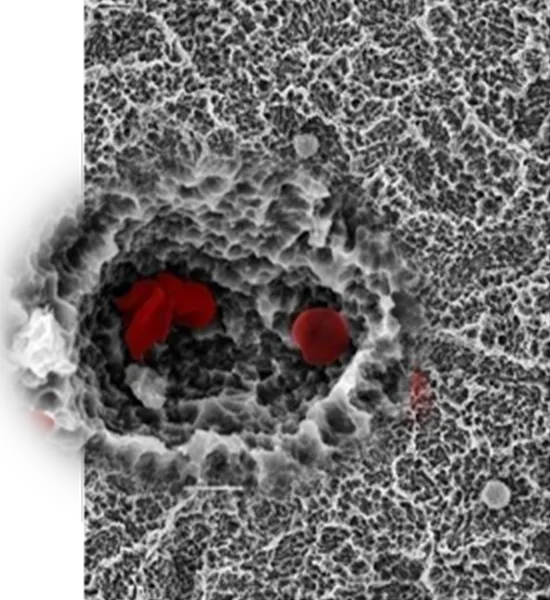

Fibrin Network

The SOI surface promotes formation of fibrin network compared to conventional surfaces.